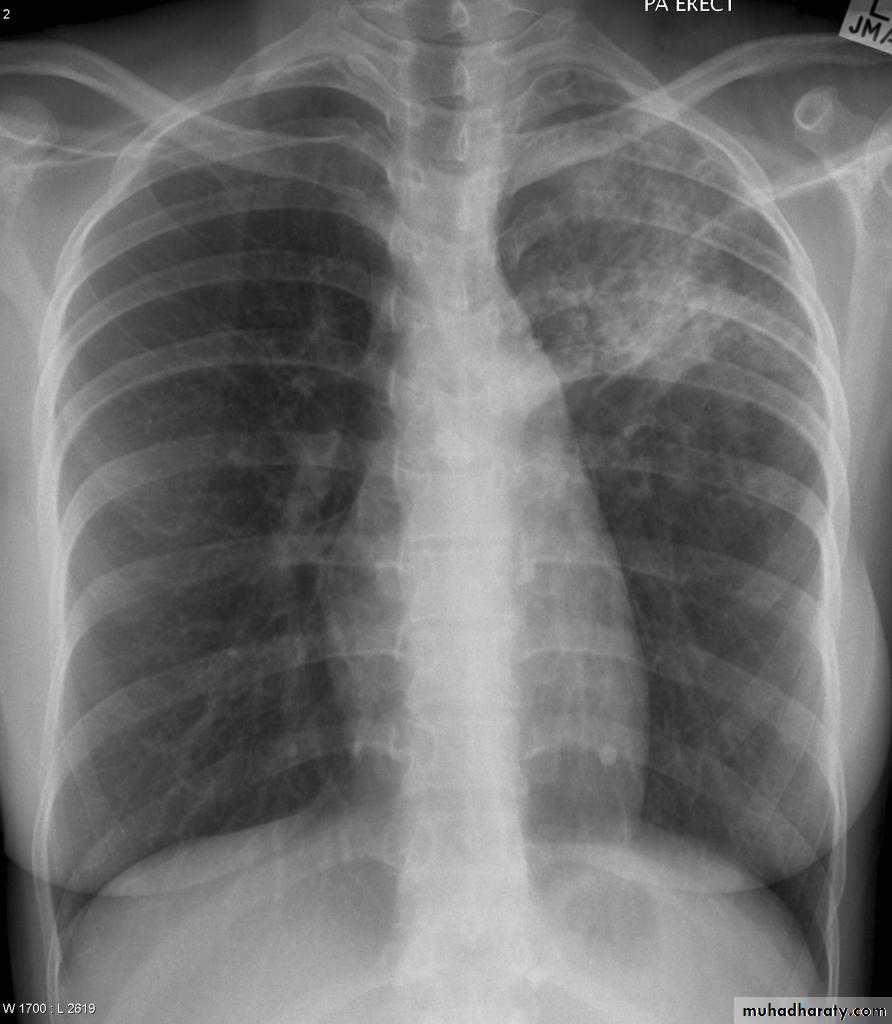

Post primary TB radiographic appearance

Post-primary pulmonary tuberculosis, also known as reactivation tuberculosis or secondary tuberculosis occurs years later, frequently in the setting of a decreased immune status. In the majority of cases, post-primary TB within the lungs develops in either :

* posterior segments of the upper lobes

*superior segments of the lower lobes

Typical appearance of post-primary TB

1.patchy consolidation or poorly defined linear and nodular opacities in both apices , upper zone in one lung , & lower zone in other lung ( ulternating lesion ) .2. Post-primary infections are far more likely to cavitate with multiple abscess formation & air fluid level more develop in the posterior segments of the upper lobes.

3. Tuberculomas seen in post-primary TB and appear as a well defined rounded mass typically located in the upper lobes .